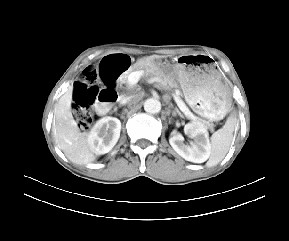

标题: CT19533:病变来源于哪?

患者,男,发现上腹部包块两月余。

病变位于肝胃间隙,实际就是位于小网膜囊(左肝下后间隙),呈轻度不均匀性强化,腹腔内及腹膜后见多发肿大淋巴结。所以我考虑肝胃间隙恶性胃肠间质瘤并淋巴结转移。

病灶与胰腺分界不清,来源于胰腺?

强化后病变与胃壁分界清楚,并且血供不是来源胃壁血管。考虑胰腺颈体癌并腹腔腹膜后淋巴结转移。